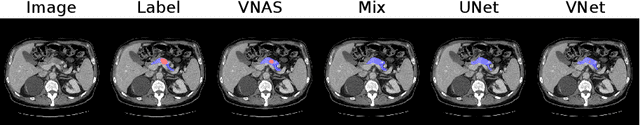

Abstract:Deep learning algorithms, in particular 2D and 3D fully convolutional neural networks (FCNs), have rapidly become the mainstream methodology for volumetric medical image segmentation. However, 2D convolutions cannot fully leverage the rich spatial information along the third axis, while 3D convolutions suffer from the demanding computation and high GPU memory consumption. In this paper, we propose to automatically search the network architecture tailoring to volumetric medical image segmentation problem. Concretely, we formulate the structure learning as differentiable neural architecture search, and let the network itself choose between 2D, 3D or Pseudo-3D (P3D) convolutions at each layer. We evaluate our method on 3 public datasets, i.e., the NIH Pancreas dataset, the Lung and Pancreas dataset from the Medical Segmentation Decathlon (MSD) Challenge. Our method, named V-NAS, consistently outperforms other state-of-the-arts on the segmentation task of both normal organ (NIH Pancreas) and abnormal organs (MSD Lung tumors and MSD Pancreas tumors), which shows the power of chosen architecture. Moreover, the searched architecture on one dataset can be well generalized to other datasets, which demonstrates the robustness and practical use of our proposed method.